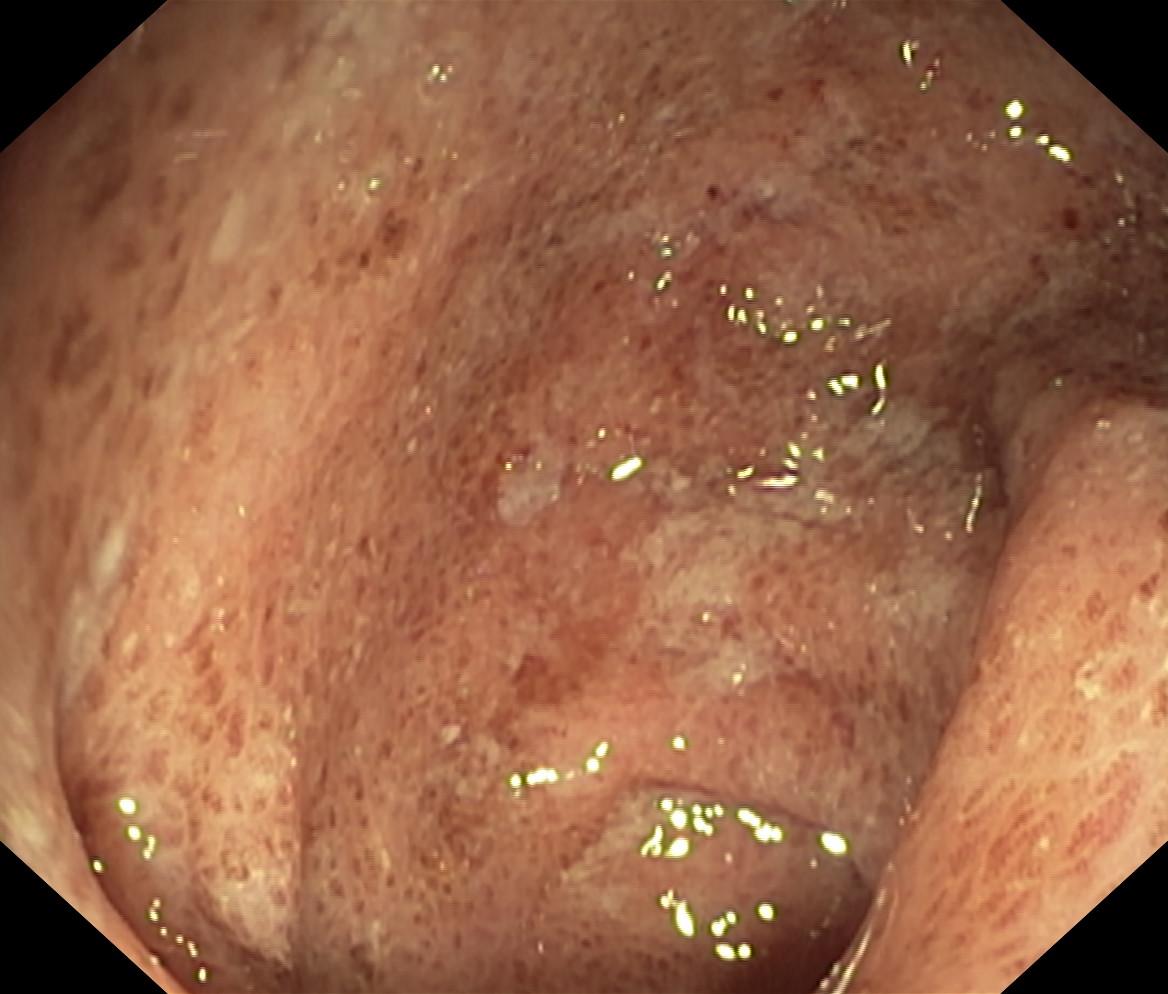

Zapalenie wrzodziejące jelita grubego